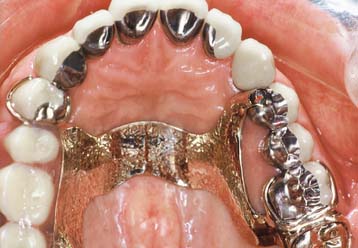

Patients with cast restorations should attend recall visits at least every 6 months. Less frequent recall may lead to oversight of recurrent caries or the development of periodontal disease. Patients who have been provided with extensive fixed prostheses (Fig. 32-6) need more frequent recall appointments, particularly when advanced periodontal disease was present. The appointments can be coordinated by the restorative dentist or the periodontist. To ensure treatment continuity, it is imperative to establish in advance who will assume primary responsibility for coordinating recall appointments.

Fig. 32-6 Patients who have received extensive treatment of this nature require more frequent follow-up care.